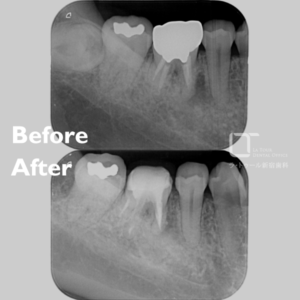

セラミック治療・40代(女性)|「歯科治療への恐怖心が強い方に静脈内鎮静下で3本同時修復」

治療内容 セラミック治療(アンレー) 施術費用 88000円×3本(別途鎮静代) 通院回数 2回 通院期間 メリット 審美性に優れており、天然歯に近い自然な色や形に仕上がります。金属を使わないため、金属アレルギーの心配がなく、高い適合精度と耐久性によって、美しさと機能を長く維持しやすくなります。 リスクと副作用 セラミック治療は保険適用外(自由診療)です。強い衝撃や過度な力が加わると、まれに割れることがあります。治療後にしみる症状がみられることがありますが、多くは時間とともに落ち着いていきます。 セラミック治療の治療例です。歯科治療に対する恐怖心が強く、 […]